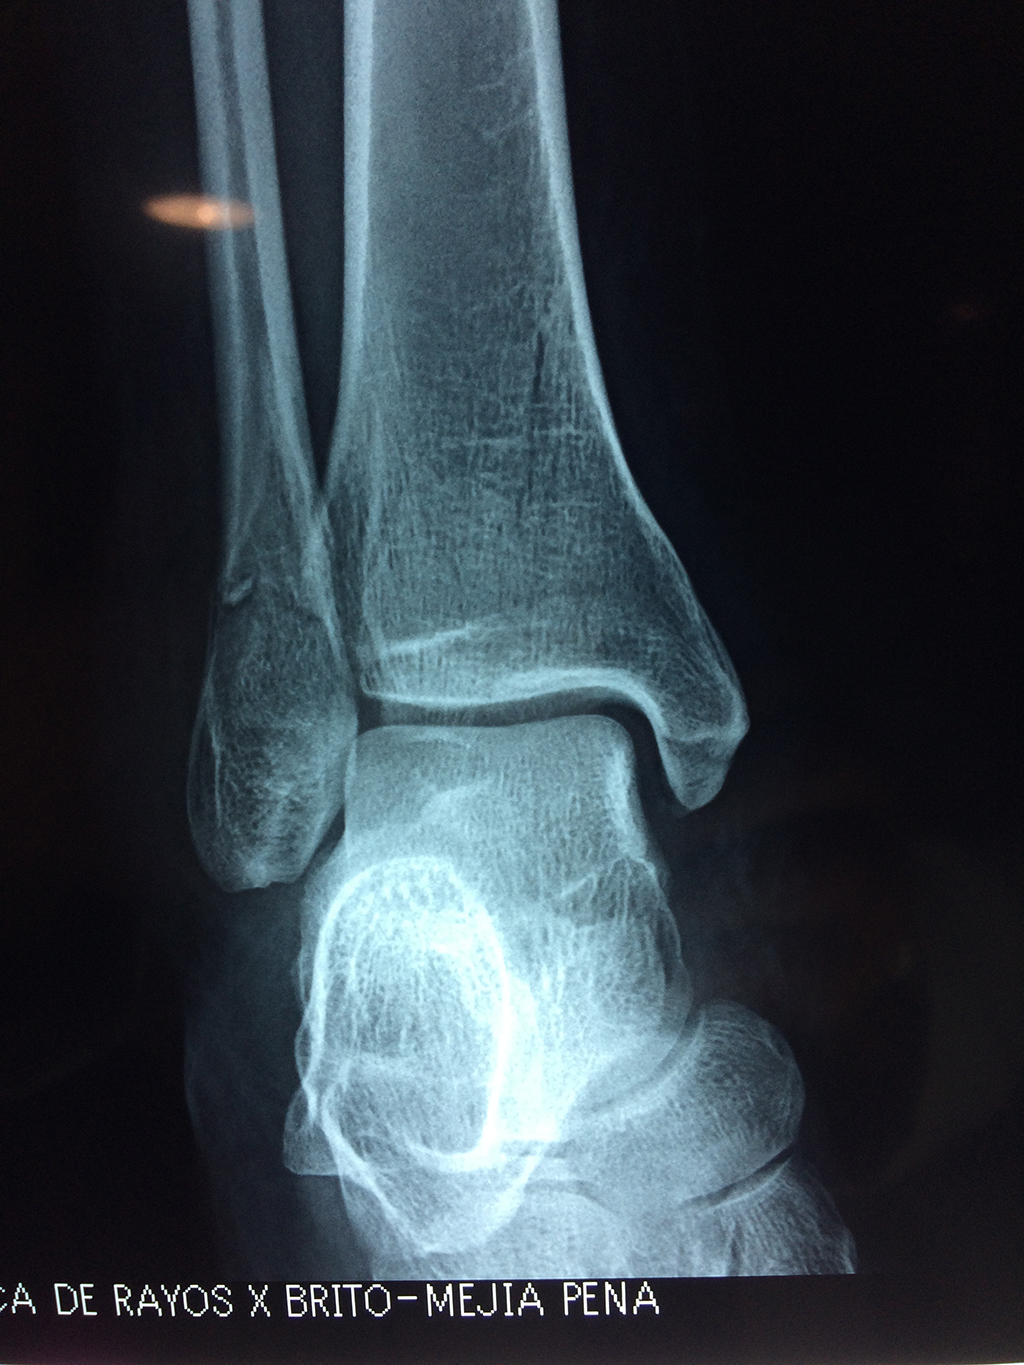

Una fractura de tobillo es la rotura de uno o más de los huesos del tobillo. Estas fracturas pueden ser:

- Parciales (el hueso está sólo parcialmente fisurado, no del todo).

- Completas (el hueso está perforado y está en 2 partes).

- Producirse en uno o ambos lados del tobillo.

- Los extremos de los huesos están desalineados entre sí (desplazados).

- La fractura se extiende hasta la articulación del tobillo (fractura intra-articular).